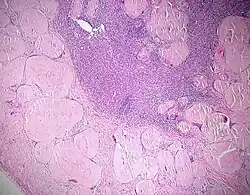

Dystrophische Verkalkung (violett) bei Lymphknotenamyloidose, H&E.